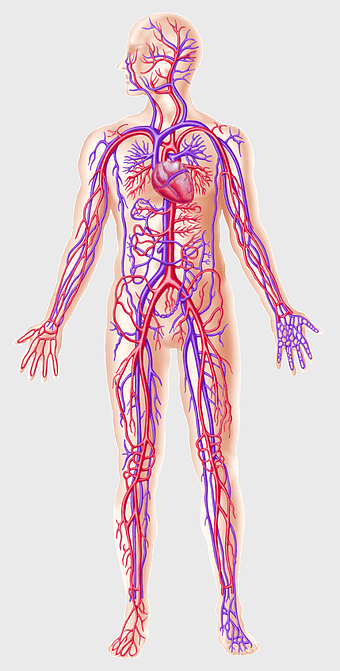

human circulatory system, blood vessel anatomy, weight loss exercise benefits, heart and artery health, vascular network visualization, cardiovascular health illustration, systemic circulation diagram -

red vascular network illustration, blood vessel line art, human body circulatory system, thrombus medical graphic, anatomical red vein depiction, cardiovascular disease diagram, artery and vein branching++) -

human circulatory system diagram, blood vessel network illustration, human anatomy chart, cardiovascular system overview, human body medical illustration, physiological system depiction, organ function visualization -